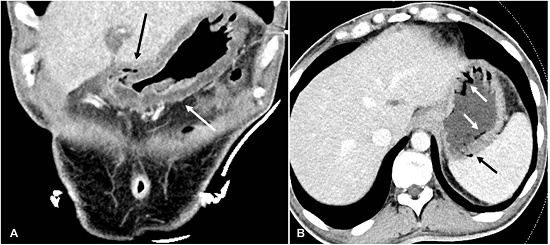

Computed Tomography (CT) scan of the abdomen showed diffuse gastric wall thickening due to edema (Figure 1A), with areas of gastric pneumatosis and venous air (Figure 1B). There was also punctate air in the superior mesenteric vein and main portal vein. No free air was noted.

CT scan of the abdomen to demonstrate gastric intramural gas is the diagnostic modality of choice. EG should be differentiated from gastric emphysema, a benign self-resolving process more often resulting from increased air pressure in the gastric cavity (instrumentation, tube insertion).15 The identification of gastric wall air in association with infectious or acute abdomen symptoms is highly suspicious for EG. This process requires prompt treatment with antibiotics and an etiological diagnostic confirmation with endoscopic evaluation. Direct examination of the stomach provides the opportunity for microbiological studies and gastric biopsies. In the case of Sarcina ventriculi infections, routine Hematoxylin and Eosin (H&E) stained biopsies are diagnostic. These organisms appear with the characteristic tetrad based “packets” (Figure 3). Micrococcus can also form tetrads, but these are significantly smaller. The thick walls of Sarcina ventriculi in silver stain, can resemble fungal structures or vegetable matter.1 (Figure 3, Inset).